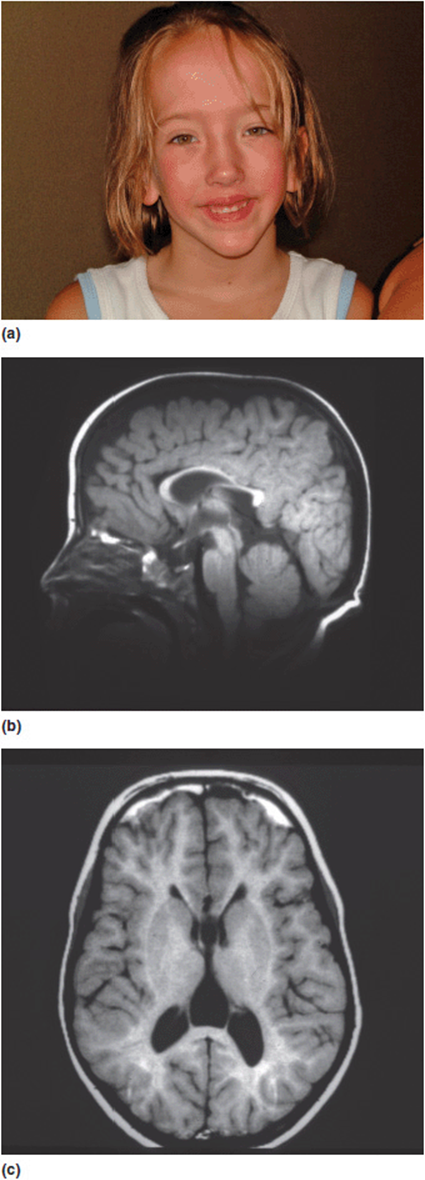

5. Abnormal regulation of other genes. Sotos syndrome is a well-described multiple anomaly syndrome. The major features of Sotos syndrome are somatic overgrowth, advanced osseous maturation, characteristic facies (down-slanting palpebral fissures, triangular chin, apparent hypertelorism), relative and absolute macrocephaly, supra-nuclear (central) hypotonia, and neurodevelopmental/neurobehavioral problems (Figure 16-10a). The vast majority of patients with Sotos syndrome also have a unique pattern of changes noted on MRI scans of the brain (Figure 16-10 b, c). Over 90% of patients with Sotos are found to have a mutation in a gene designated NSD1. NSD1 is a histone methyl-transferase implicated in transcriptional regulation. It has multiple functional domains that regulate several other genes such as the estrogen receptor, thyroid hormone receptor, retinoic acid receptor, retinoid X receptor, and nuclear receptor interaction domains. The pathogenesis of Sotos syndrome thus has to be assessed not by looking at the gene itself, but by evaluating all of the other genes it influences. Current estimates suggest that NSD1 may directly interact with over 30 other loci.

Figure 16-10. (a) Young girl with Sotos syndrome with typical facial characteristics. (b, c) Sagittal and axial MRI images of the brain of a child with Sotos syndrome showing characteristic changes.